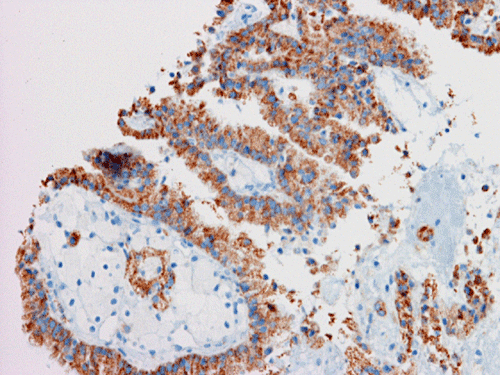

I. CD10 |

On FNA with Pap stain, clusters of cells with a papillary structure are present (Panel A). A delicate fibrovascular core can be seen at the center (arrow in Panel B). In higher magnification, two population of cells are present. While one of the population appears as solid sheets of polygonal epithelial cells with increased nuclear cytoplasmic ratio and distinct cell border (arrow head in Panel C), there are also many cells with distinctly foamy cytoplasm, lower nuclear cytoplasmic ratio and bland nuclei, and indistinct cell border (arrow head in Panel C). The foamy cells are most consistent with foamy macrophages. A distinct nucleoli is present in the epithelial cells (Panel D). The papillary morphology is well demonstrated in the cell block (Panel E, F, and G). Characteristically, the papillary structures are formed by a central core of foamy macrophages and covered by a epithelial cells. The epithelial cells but not the foamy macrophages are immunoreactive for CD10, AMACR, and CK7 (Panel H, I, and J).

Immunohistochemically, PRCCs are positive for CK7, a-methylacyl coenzyme A racemase (AMCAR), and CD10.